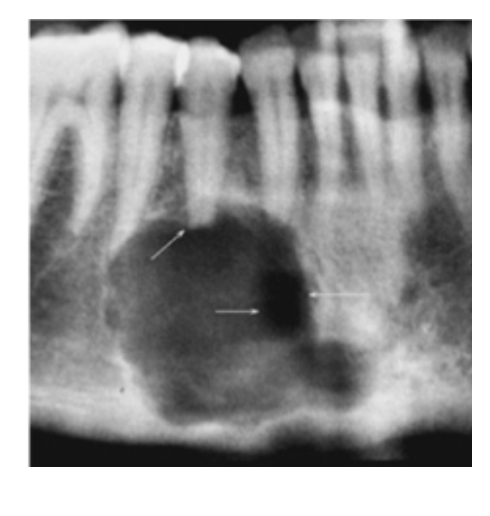

Aneurysmal Bone Cyst

Pseudocyst w/ blood-filled spaces

Posterior Mandible

* Multilocular Radiolucency:

* Expansile

Tx: Fine Needle Aspiration 1st (Blood=Confirms Dx)

* Excision